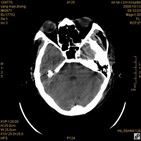

术前CT

术前CT1 术前CT2 术前CT3 术前CT4